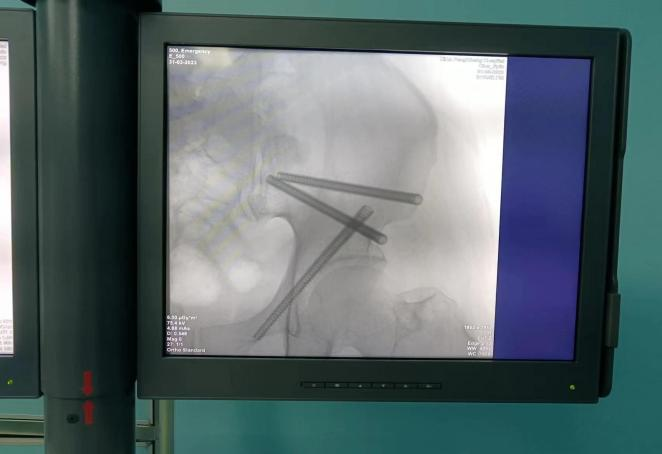

骨科机器人定位、攻入导针

钻孔置钉、手术切口